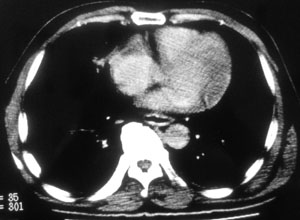

性别 男  62岁 因咳嗽及左肱骨剧烈痛疼数天来院检查。

右中央型肺癌并肱骨转移。

考虑右肺中叶肺癌并左肱骨转移伴病理性骨折。

支持右肺中心型肺癌并肺内及左肱骨转移伴病理性骨折

右肺中心型肺癌并中叶不张,左肱骨溶骨性转移并病理骨折。